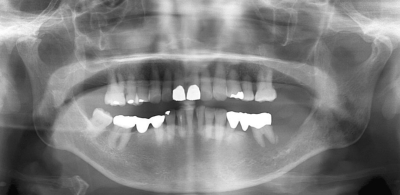

78歳の女性。抜歯後の治癒不全を主訴として来院した。左側の下顎臼歯部歯肉に硬結を伴う潰瘍を認め、左側顎下部に無痛性の腫脹を認める。初診時のエックス線写真、造影CT横断像と冠状断像及び下顎歯肉部の生検時のH-E染色病理組織像を別に示す。

矢印で示すのはどれか。1つ選べ。